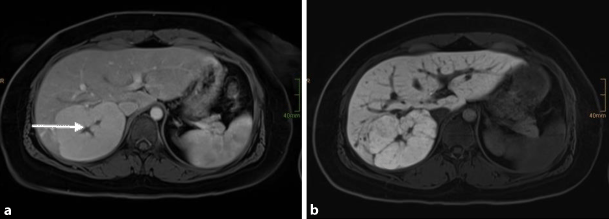

HCA is a rare, solid and benign liver tumour of presumable epithelial origin. The estimated prevalence is about 0.004%. These lesions occur mostly in women of childbearing age and seem strongly associated with the use of OCPs and oestrogens [36]. Women older than 30 years taking OCPs for longer than 5 years have the highest risk levels. A causal role for hormone activity in HCA growth is suggested by data linking adenoma regression to the cessation of OCP use and, vice versa, growth associated with pregnancy [37]. Hepatic adenomas appear as single or multiple lesions and may occasionally reach a size larger than 20 cm. Hepatic adenomatosis is an equally uncommon condition in which >10 nodules develop in the absence of classical risk factors such as OCPs. There is a strong association seen with glycogen storage disease. As shown in Fig. 3, HCA is usually detected by imaging, typically US or multi-phase contrast-enhanced imaging studies such as CT or MRI scans. The significance of making a specific diagnosis is that, unlike haemangioma and FNH, HCA has a small but meaningful risk of progressing into malignancy. Although imaging provides supportive information, a definitive diagnosis of hepatic adenoma requires biopsy of the tissue [38]. The introduction of a new classification system for HCA helps clinicians in tailoring the treatment. Patients are stratified according to imaging criteria, expression profile of associated immunohistochemical markers or molecular findings. This classification includes hepatocyte nuclear factor 1α-inactivated HCA (H-HCA 30–35%), β‑catenin-mutated HCA (b-HCA 10–15%), inflammatory HCA (I-HCA 50%) and a subgroup of unclassified cases (less than 10%) [39]. The b‑HCA group appears to be related to hepatocellular carcinoma [38].

Fig. 3

HCA: axial venous phase MRI with Primovist® (Bayer Schering Pharma, Berlin, Germany) shows an only slightly hyperintense lesion (arrow) in the centre of the liver (a) with a marked capsule. In the hepatobiliary phase no uptake of contrast agent is seen within the lesion (arrow), which is further consistent with HCA (b) [9]